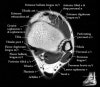

발목 관절의 MRI 단면 영상

- Axial section

Axial PD fat suppression evaluates the tendons and ligaments of the ankle particularly after acute/subacute injuries. It also is sensitive to talar dome osteochondral defects. Alternatively, a T2 sequence can be used to eliminate magic angle artifact that may occur as the tendons travel around the malleolar turns.

Tibiofibular ligaments

Lateral ankle ligaments

Deltoid and spling ligaments

Tendon(Achilles, Medial, Lateral, Anterior)